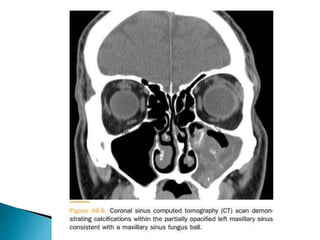

 Commonly only a single sinus is affected by the

predilection for the maxillary sinus followed by the

sphenoid sinus. The frontal and ethmoid are less

often affected. A clue to the diagnosis includes soft

tissue density within the sinus with/without foci of

calcific deposit. Postobstructive change may be

observed if the mycetoma obstructs the sinus

drainage pathway leading to partial or complete sinus

opacification 2.

 Evidence of chronic inflammation with sclerosis and

thickening of the wall of the paranasal sinuses.

Careful evaluation of the sinus cavity is prudent to

exclude bone erosion that is not a feature of

mycetoma / chronic fungal sinusitis rather a feature

of acute invasive fungal sinusitis